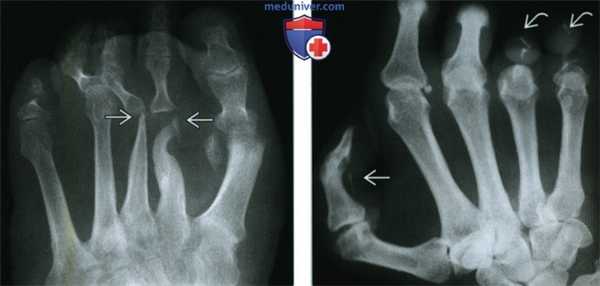

• Рентгенография:

о Образование (-я) мягких тканей

о Эрозии вдавления на кости, могут быть обширными и создавать картину «талого снега»

о Кости становятся изогнутыми, с расширением межкостных промежутков

о На поздних стадиях заболевания визуализируется обширное сращение костей

(Слева) Рентгенография в ПЗ проекции: визуализируются большие вдавления вдоль медиального и латерального краев средней трети стопы и обширное сращение костей в межплюсневых, плюсне-предплюсневых и межпредплюсневых суставах. Отмечаются остаточные дефекты, эрозии от вдавления.

(Справа) Сагиттальное Т1ВИ C+ FS МР-И, этот же пациент: обширное внутрикостное усиление и воспалительные изменения мягких тканей. На такой поздней стадии костные изменения преобладают над изменениями мягких тканей. (Слева) Сагиттальное Т1 ВИ: большое образование мягких тканей вдоль подошвенной поверхности стопы. Образование деформирует прилегающие плюсневые кости, которые искривлены. Изменения костного мозга в плюсне указывают на костную инвазию.

(Справа) Сагиттальное Т1 ВИ С+МР-И, этот же пациент: множественные образования мягких тканей и внутрикостные очаги некроза. Были выявлены множественные дренирующие свищи. Отделяемое свищей имело зернистую консистенцию вследствие скопления микроорганизмов.